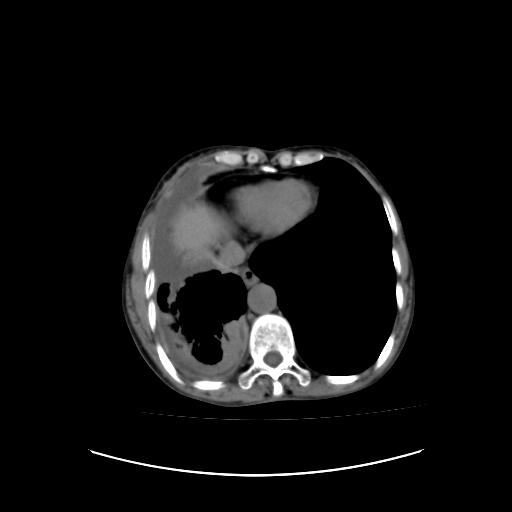

标题: CT16930:女 59 胸痛6个月 胸水脱落细胞学见瘤细胞 [打印本页]

可见多发肺内病灶,且胸膜病灶较多有圆球状而非丘状,多考虑胸膜转移瘤伴胸腔积液,右侧胸廓缩小固定,且部分病灶呈丘状,尚不除外恶性胸膜间皮瘤伴肺内转移

右侧胸膜增厚,局部呈结节状增厚,右侧胸腔少量积液。双肺未见确切肿块影。纵隔未见淋巴结肿大。气管、支气管通畅。考虑右侧胸膜间皮瘤(恶性?)可能性大。不除外癌性胸膜炎。

恶性胸膜间皮瘤伴肺内转移可能性大;或胸膜、肺内均为转移瘤,左肺下叶亦见多发小结节影。

右侧胸廓塌陷,右侧胸膜广泛增厚并见多发胸膜结节,右侧少量胸腔积液并包裹。

右侧广泛胸膜增厚,局部呈结节状增厚,右侧胸腔少量积液。双肺未见确切肿块影。纵隔未见淋巴结肿大。气管、支气管通畅。考虑右侧胸膜间皮瘤(恶性?)可能性大。支持!

右侧胸膜转移瘤,原发灶可能就在在右肺,另外建议检查右侧乳腺.

右胸腔结节均考虑来自胸膜(部分来源于叶裂),考虑胸膜间皮瘤或转移瘤.